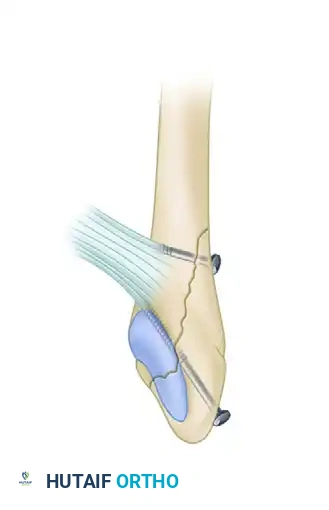

Image

FIGURE 54-5: Bimalleolar ankle fracture featuring an oblique fracture of the lower fibula treated with interfragmentary screw fixation. Kirschner wires were utilized for the internal fixation of the medial malleolus.